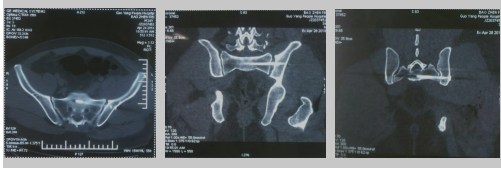

二 髋 臼 骨 折常见于高能量损伤,多合并髋关节脱位,以后脱位为主。

■ 骨折的粉碎和移位程度,负重区的损伤程度及骨折的复位质量是获得远期疗效的根本因素。

■ 正确的诊断,合适的手术入路,精湛的手术技术,实用的手术器械是良好预后的必要条件。

■ 手术治疗的目的是恢复髋臼的正常解剖结构,恢复关节内正常的压力分布。

■ 髋臼骨折为关节内骨折,需要解剖复位,坚强内固定。

■ 髋臼骨折后导致股骨头与髋臼之间失去正常的解剖对应关系,股骨头与髋臼的接触面积明显减少,关节面负重不均匀,导致创伤性关节炎。